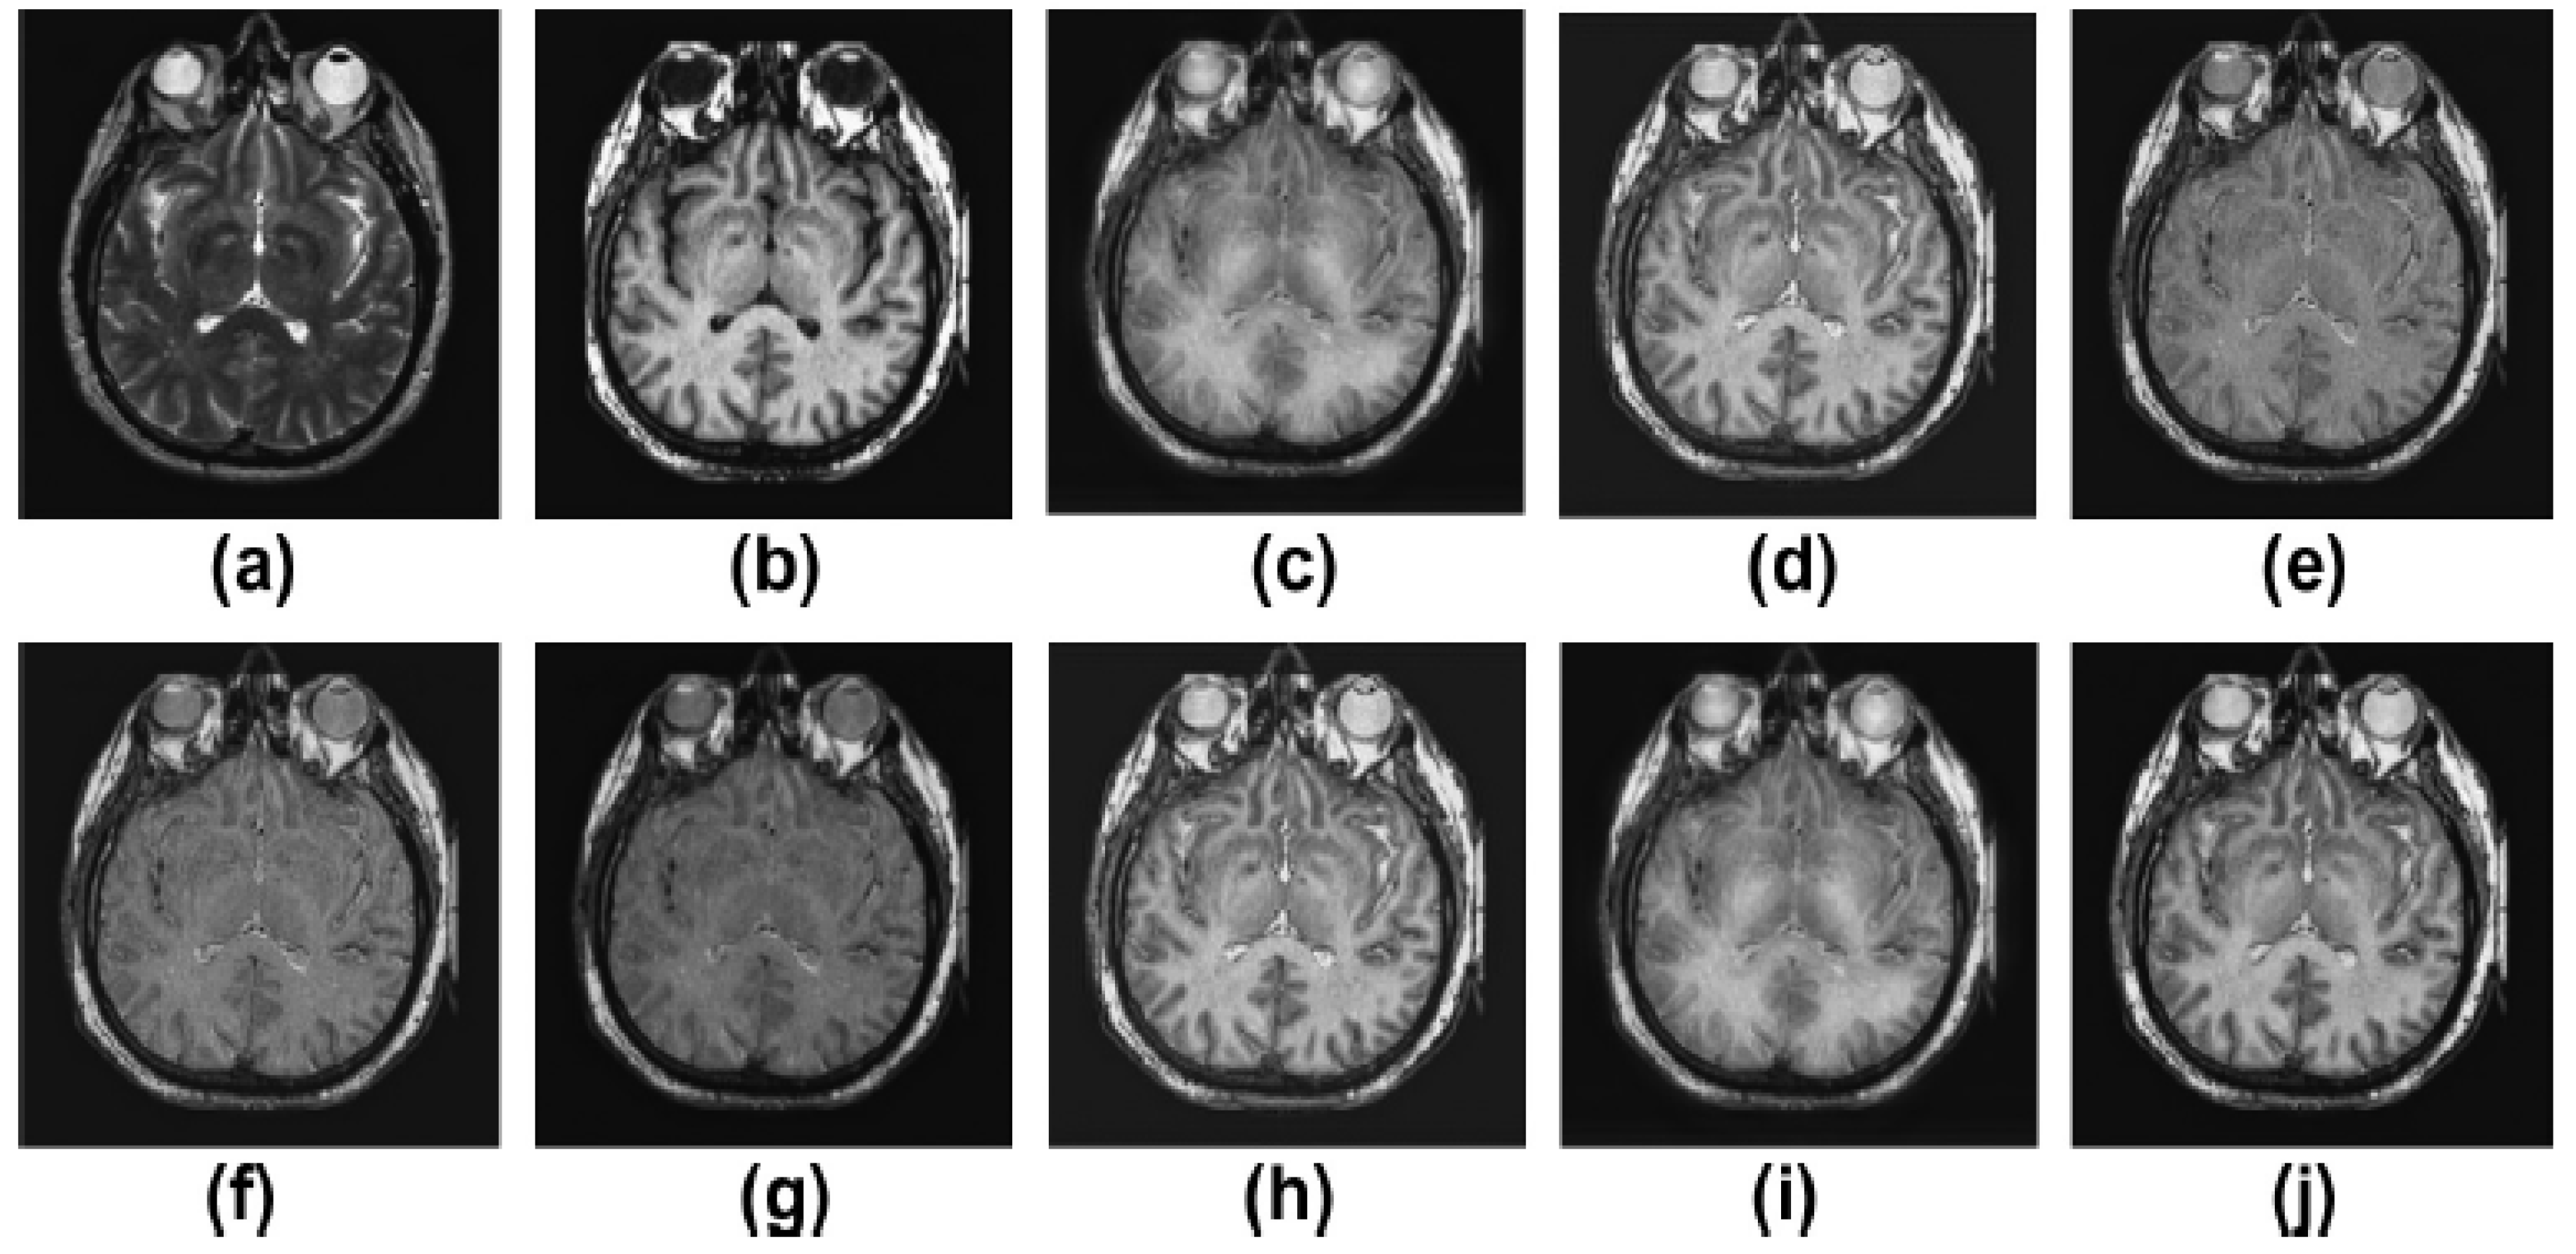

5.2. Results and Discussion